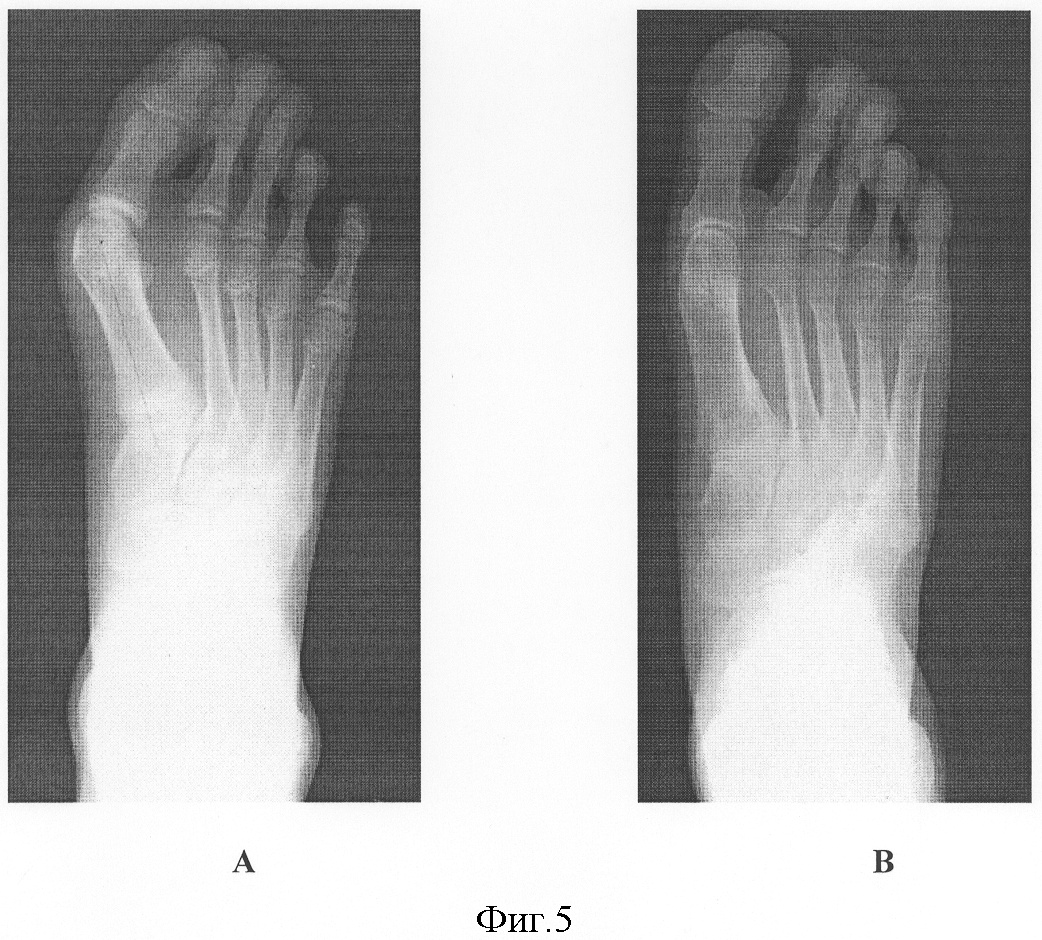

фиг.5 – рентгенограммы больной С., 13 лет:

А – до операции;

В – через 8 месяцев после операции предлагаемым способом.